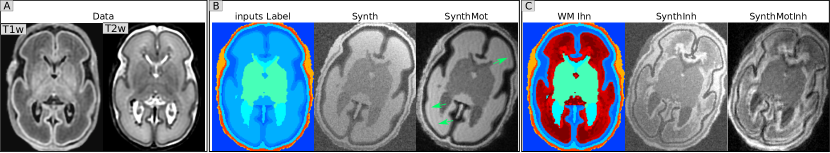

Motion simulation (Mot). We then extend the data augmentation beyond Billot et al., (2023) by adding a RandomMotion transform to simulate subject motion during the MRI acquisition. We use our own implementation of the motion simulation introduced in Reguig et al., (2022), which allows us to simulate a realistic time course of rigid head motion. As shown in Fig. 2, the motion simulation induces inhomogeneities in the different tissues because of the tissue mixing in the k-space induced by motion. We use a maximum displacement sampled from U[3, 8] (in mm) for the translation and U[3, 8] (degrees) for the rotation. Note that we force the background signal intensity to zero when generating motion artifacts to avoid mixing background intensity with the motion process.

White Matter inhomogeneities (Inh). Inhomogeneities in the WM tissue are expected during the developmental period covered, and are visible in the MRI data. We adapted the method proposed by Billot Billot et al., (2023) to account for such variations within a label: we subdivide WM into smaller sub-regions by clustering the T2w intensities, within the WM mask, using the Expectation Maximization algorithm Dempster et al., (1977). We choose N regions ( N[2,3,4,5,6]𝑁23456N\subseteq[2,3,4,5,6] ) in order to represent the inhomogeneities with different levels of granularity. Each subregion is then considered as a distinct tissue in the generative model (thus with a different random intensity) but they are regrouped for the segmentation objective in order to predict the whole WM. (see Fig. 2 c). Note that the term ‘transform’ is used for simplicity but is not adapted here since it is only a fixed modification of the input labels. Note also that real T2w data is used only for the generation of the label maps, but no real data is used for generating the synthetic images.

Refer to caption

Figure 2: Illustration of the synthetic datasets obtained from one individual data. A) the T1w and T2w MRI data from this subject; B) and C) show respectively the 2 different label maps (in color) used as input of the generative model (without and with additional labels in the WM to simulate inhomogeneities). For each label map, we show an illustrative example of augmented synthetic images, corresponding to the 4 synthesis-based models. Green arrows indicate subtle artifacts induced by motion simulation.